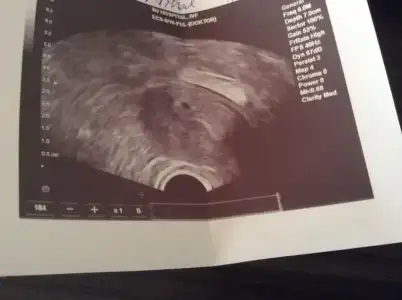

Son bi kez daha kanda baktır canım belki geç döllenmedir. Ama çıkmazsa kanda mutlaka doktora görün,, kist falan vardır ya da vs vs.. İhmal etmee

Buyuk bir ihtimalle gec yumurtlamissindir. Ne zaman yumurtlarsan yumurtla, o catladiktan sonra 13-16. gun icinde adet oluyorsun. Eger bi durumdan dolayi vucudun yumurtlamamis yada gec yumurtlamissa, adetinde onun icin gecikiyor canim. bende oyle olmustu hemde 2 ay gecikmisti. Doktor bunun her kadina olabilecegini soyledi, stres, hava degisimi vs. den kaynaklaniyormus

Teşekkür ediyorum yorumlarınız için arkadaşlar. Beklemedeyim